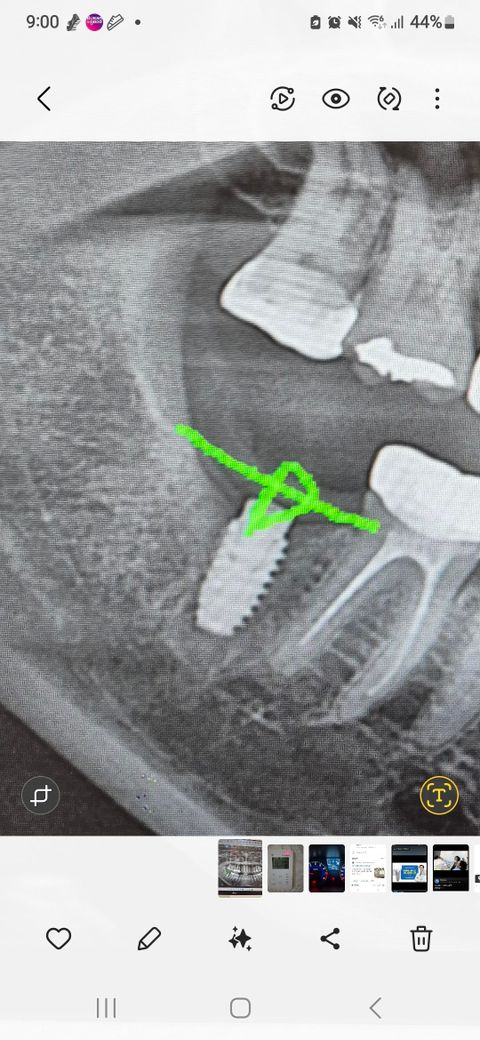

임플란트재수술후염증이없어도통증이있을수있나요?

임플란트1차에 너무 깊게 심어서 머리올린 후 극심한 통증으로제거하니통증이사라졌어요.두달 후 다시심었는데 일주일후부터 비슷한 통증으로 3주째 시달리고있어요.그때도 그렇고 이번에도 앞치아까지 같이 욱신하게 아픈데..사진상 이상 소견은 없다고 하여 다음주쯤 열어서 보자고 하세요..심고나서 일주일 후부터 통증이 생겼는데 앞치아 때문은 아니겠죠?그때도 그생각했었는데 빼고나니 안아팠거든요.그때열어보고 고정력이 약하거나 빼고 싶으면 빼주신다는데 일단 통증이 심하니 빼는게 나을까요?사진첨부할께요

치과에서 제시하는 방법대로, 현재 통증이 심하고 지속된다면 다시 나사를 빼고 상태를 확인하는 것을 권합니다. 통증이 계속되거나 불편함이 계속될 경우, 임플란트를 빼고 다시 재수술을 고려하는 것이 필요로 될수 있습니다.

엑스레이 상으로는 크게 문제가 잇어 보이진 않는거 같습니다. 그래도 통증이 잇다면 임플란트를 제거하고 나서 시다려보셔야될것같습니다.

일반적으로 임플란트가 잇몸 뼈와 유착이 되고 나면 아무런 느낌이 없는 것이 정상입니다. 불편감이 크다면 임플란트 프리와 치조골의 유착이 잘못되었을 가능성이 높습니다.

이런 경우에는 임플란트를 제거하고 수술해야 할 수 있으니까. 자세한 확인을 위해서 치과에서 진료를 받아보세요.